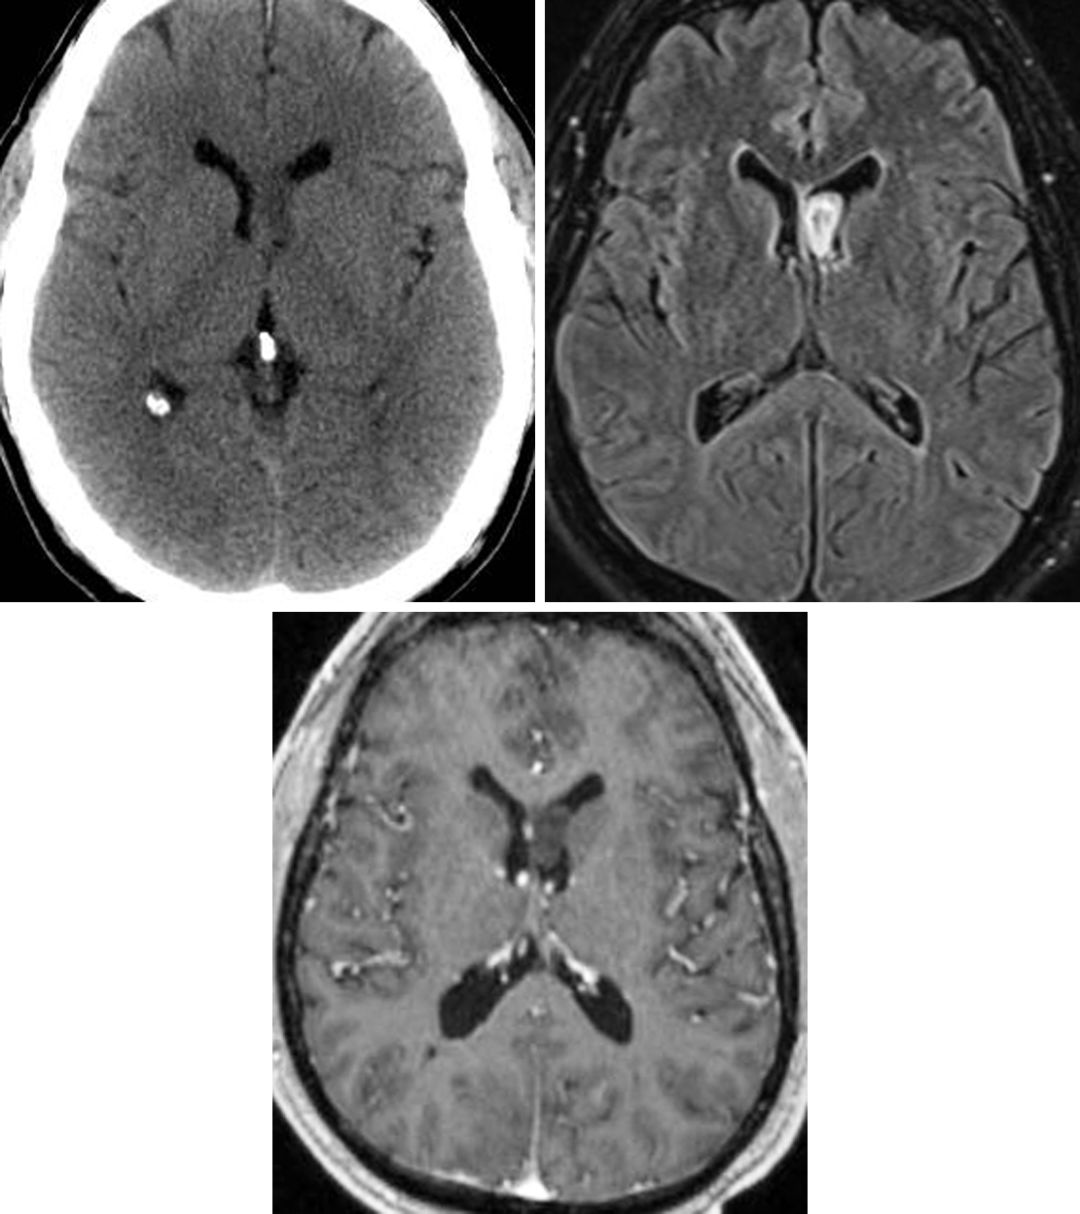

图1. 脑室内小结节状室管膜下瘤,在FLAIR加权相上呈高信号(左),是一种少见的良性肿瘤。增强后有多种表现,这例在T1增强加权相后无明显强化(右)。

图2. 脑室内室管膜下瘤在CT上不易辨别(左上),而在FLAIR加权相上显示比较清楚(右上)。这例左侧脑室额角室管膜下瘤在T1增强加权相后未见明显强化效应(下)。